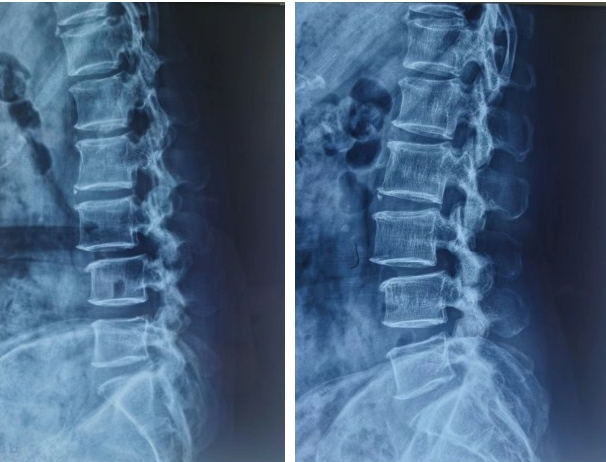

术前检查显示,患者的腰3/4椎间失稳。